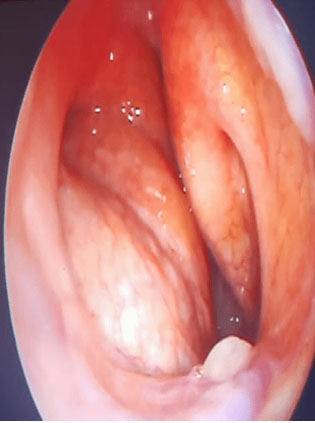

A 49-year-old male presented in our department with gradually progressive swelling in right cervical region for 8 years. The patient also complained of voice change for two months and decreased hearing in right ear for one month. Palpation revealed approximately 3 × 3.5 cm firm, non-tender, non-pulsatile, fixed swelling in right cervical region just below the angle of mandible. Oral cavity examination revealed firm, non-tender, non-pulsatile swelling medializing the right tonsil (Figure 1). Nasal endoscopy and laryngoscopy revealed a bulge in the nasopharynx and parapharyngeal space (Figure 2). Otoscopic examination demonstrated otitis media with effusion in right ear. There was no significant cervical lymphadenopathy. Cranial nerve examination was normal. Contrast enhanced magnetic resonance imaging (MRI) presented a 7 × 3.5 × 8 cm heterogeneously enhancing and circumscribed elongated soft tissue mass extending from submandibular area to parapharyngeal, tonsillar, and retromolar region with encasement of great vessels on right side (Figure 3).

Figure 1: Preoperative intraoral image showing right tonsillar bulge.